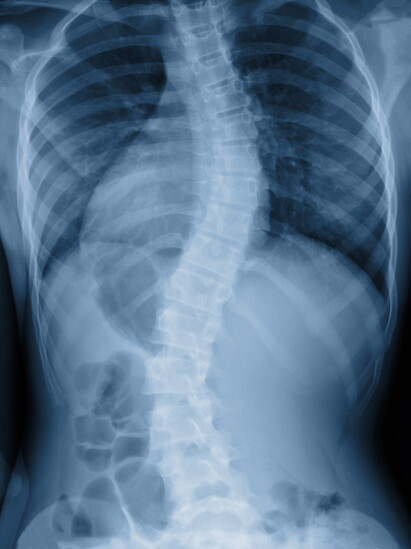

Scoliosis and Spinal Deformity Expertise

Dr. Kraus specializes in the conservative treatment of adult and adolescent scoliosis, kyphosis, and spondylolisthesis— conditions that can cause pain, fatigue, and progressive spinal collapse. His goal, he explains, is simple but ambitious: “These are collapsing deformities of the spine— and our mission is to stop that collapse.”

At Bethesda Spine & Posture, patients receive individualized care plans that may include CBP corrective traction, posture-specific exercise, and custom ScoliBrace® 3D bracing. Each brace is designed using a patient’s X-rays, photos, and 3D iPad scans, ensuring an exact fit that promotes spinal elongation, midline alignment, and de-rotation.